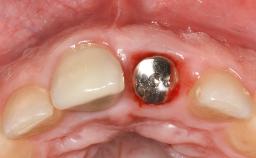

Surgical Management of Peri-Implantitis: Removal of Implant Due to Recurrent Infection Using an Implant-Retrieval Tool

Despite anti-infective surgical treatment, some patients may experience recurrent infection and progressive bone loss requiring additional treatment. This case describes a conservative approach using an implant retrieval tool without the need for excessive bone removal or use of a trephine.

A 65-year-old female patient was referred to the periodontist for assessment and management of infection associated with an implant at site 12. The general dentist had noted suppuration on probing during examination.